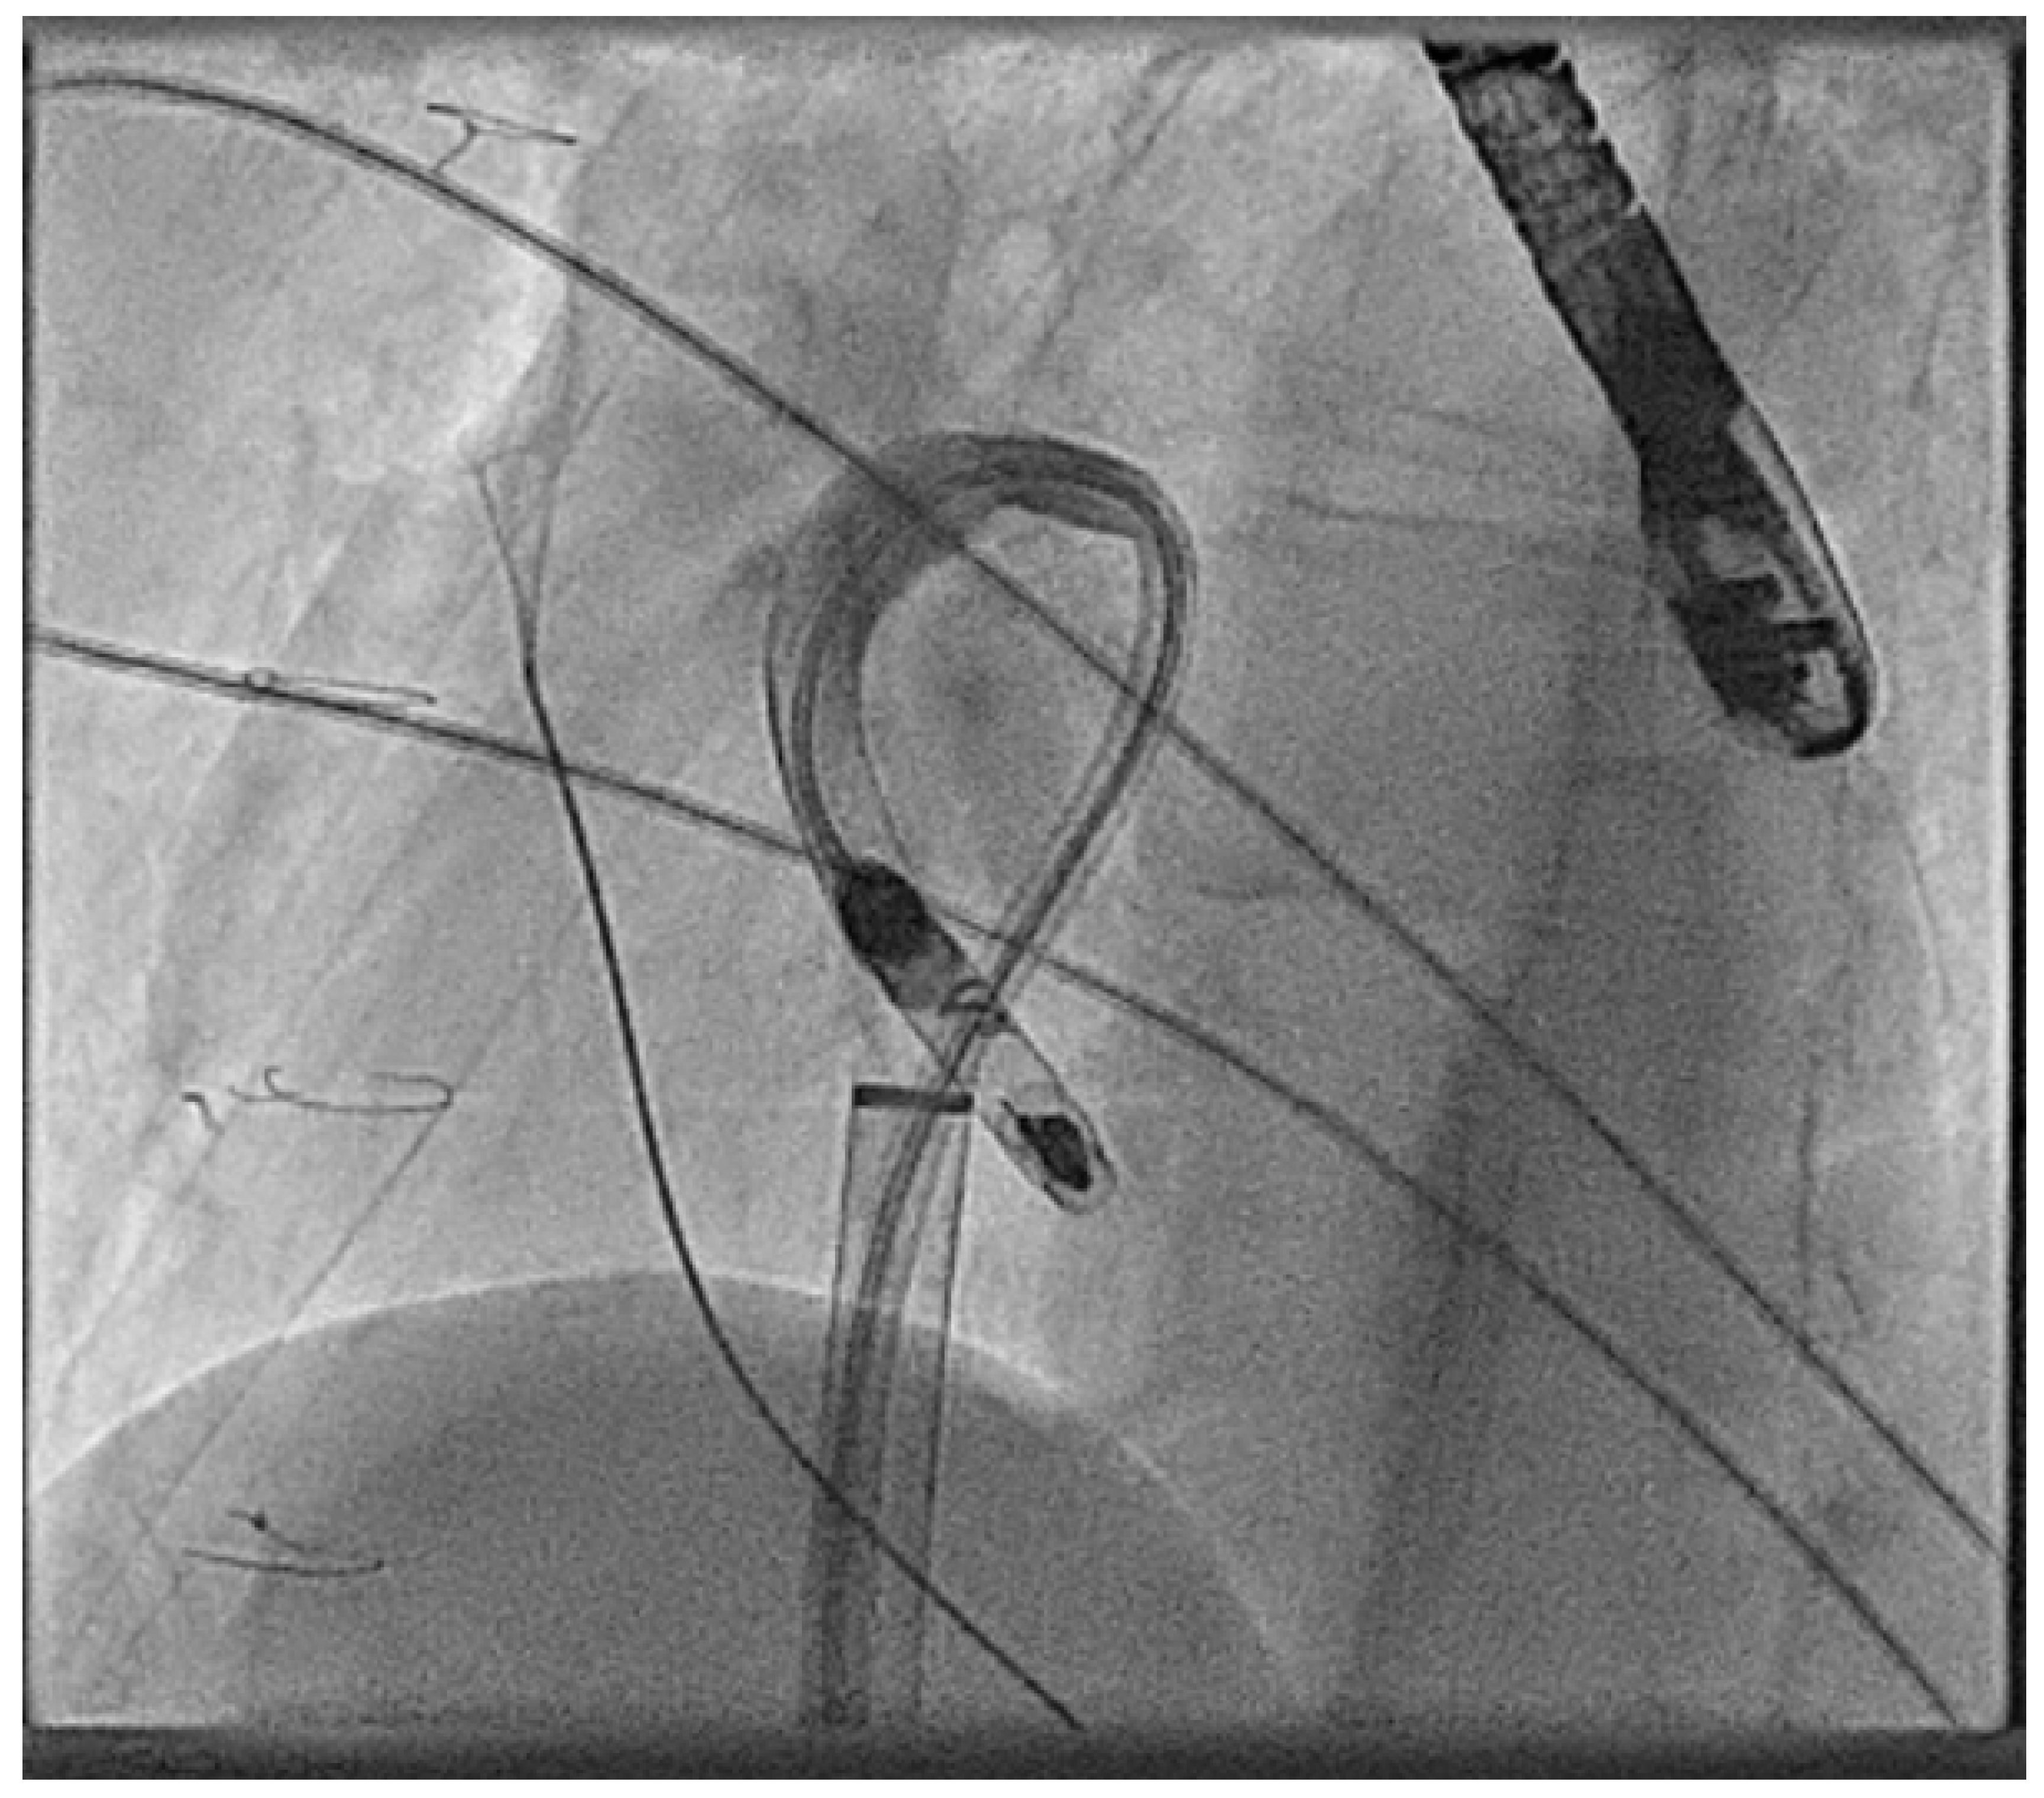

- Hayle, P.; Altayeb, F.; Hale, A.; Rao, A.; Ashrafi, R. Case report demonstrating novel approaches for leadless pacemaker implantation in the single ventricle heart. Eur. Heart J. Case Rep. 2025, 9, ytaf146. [Google Scholar] [CrossRef]

- Goulden, C.J.; Khanra, D.; Llewellyn, J.; Rao, A.; Evans, A.; Ashrafi, R. Novel approaches for leadless pacemaker implantation in the extra-cardiac Fontan cohort: Options to avoid leaded systems or epicardial pacing. J. Cardiovasc. Electrophysiol. 2023, 34, 2386–2392. [Google Scholar] [CrossRef]